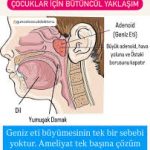

Adenoid hipertrofisi durumunda:

Östaki borusunun farengeal açıklığı direkt olarak mekanik olarak tıkanır.

Bu tıkanma, orta kulakta negatif basınç oluşmasına ve sıvı birikmesine (otitis media effüzyon) yol açar.

Adenoid hipertrofisi sadece mekanik tıkanma yapmaz;

Kronik inflamasyon, lokal ödem ve mukus üretimini artırır → Östaki borusunun tıkanmasını daha da şiddetlendirir.

💡 Klinik ipucu: Pediatrik hastalarda tekrarlayan orta kulak problemleri ve işitme kaybı varsa adenoid boyutu mutlaka değerlendirilmelidir. Adenoidektomi, Östaki borusu ventilasyonunu düzeltebilir.

Adenoid hipertrofisi Östaki borusunu mekanik olarak tıkar.

Tıkanma, orta kulakta negatif basınca yol açar.

Negatif basınç, orta kulakta sıvı birikmesine (otitis media effüzyon) sebep olur.

Kronik durumda işitme kaybı ve tekrar eden orta kulak enfeksiyonları görülebilir.